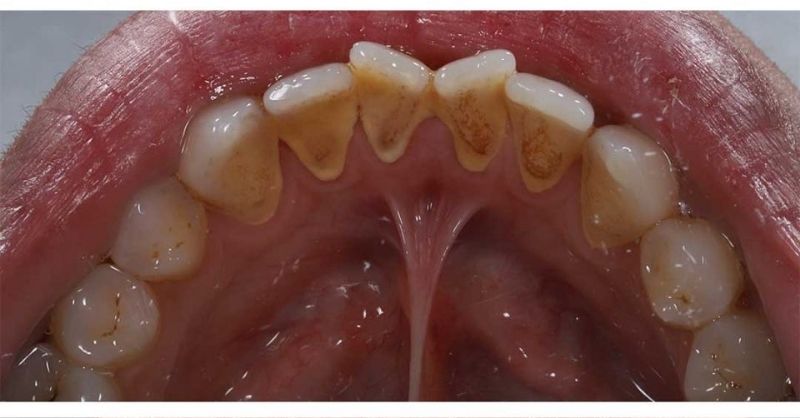

7 top hacks to get rid of unsightly tartar stains

Tartar, also known as dental calculus, is a hardened form of plaque that forms on teeth and along the gumline. It develops when plaque, a sticky film of...